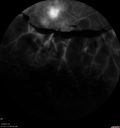

71 year old female - About 1 year ago the patient had injections in each eye and also started with laser. Hurricane Irma hit and she had her appointments cancelled and she did not go back. She had cataract surgery previously but no other treatment. About a month ago she noticed that her vision was declining in the left eye and then a few weeks ago it got a lot worse. The right eye is pretty good and she can see with her reading glasses. She is planning to get bifocals in the future. She did not want to get new glasses until we figured out the left eye. VA OD: sc20/25-2 VA OS: sc1’/200 IOP: TP: OD:15 OS:15 The left eye has no macular edema or macular detachment and an APD. The vision loss is likely from a CRAO or from optic atrophy. So a PPV was not done.

Severe PDR with preretinal fibrosis435 views71 year old female untreated for a year following injections because of hurricane Irma. VA 20/30 OD and 5/200 OS. Sudden vision loss 1 month ago left eye was likely an ischemic event. Right eye is being treated with injections and PRP laser.00000